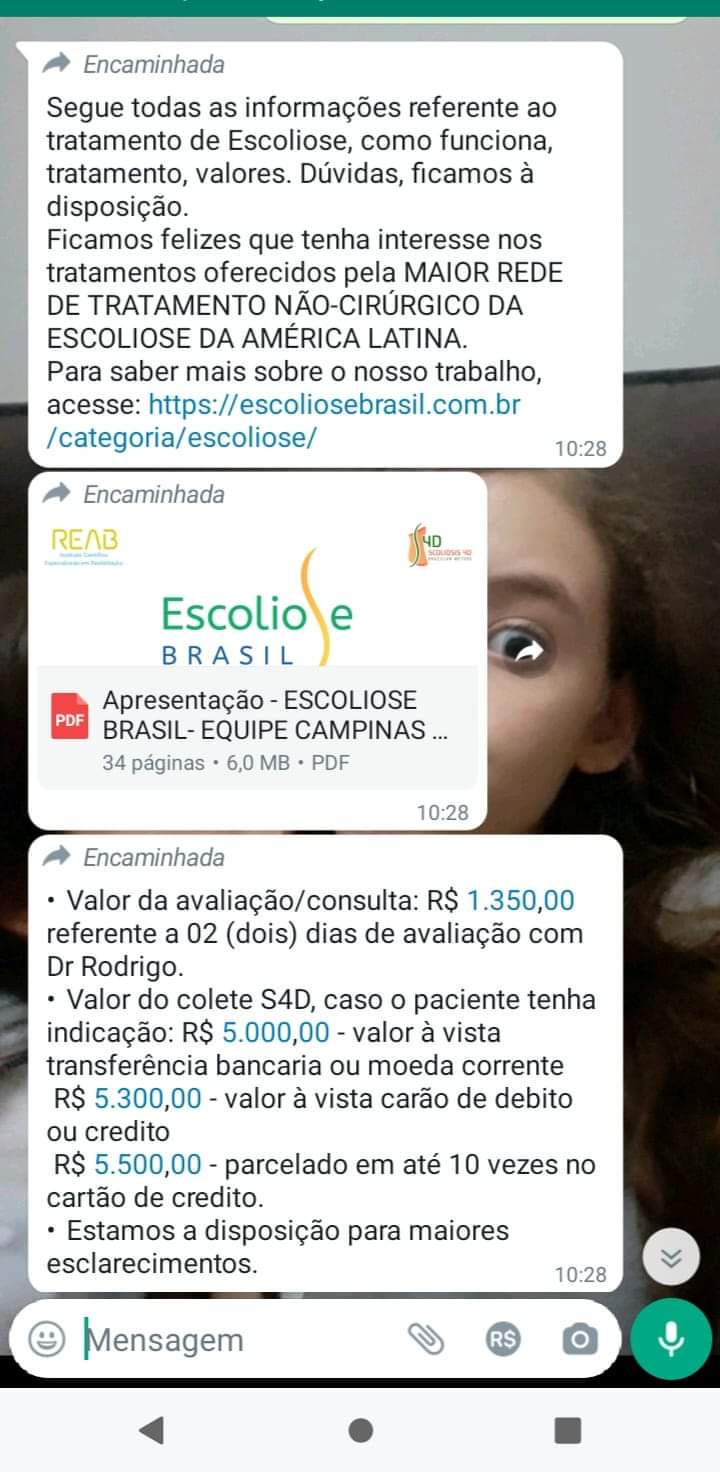

Por indicação da fisioterapeuta, descobri que tem em Campinas o Centro de Escoliose, mas é tudo particular e não temos condições.

Eu conto com meus amigos com qualquer ajuda pra mim fazer esse tratamento lá e podendo fazer uso do colete. Vou postar tudo abaixo e se quiserem pode chama no whats 19.978254763

Para me ajudar vou passar o pix do meu vozinho para qualquer ajuda e bem vinda e compartilhe para que eu possa ter uma vida mais saudável.

Quem quiser ajuda vai no do pix do meu vô, está em nome dele. 19 99593 2943. Vicente de Oliveira Rocha (Santander). O centro de escoliose fica em campinas

Escoliose Brasil . Dr Rodrigo Andrade.